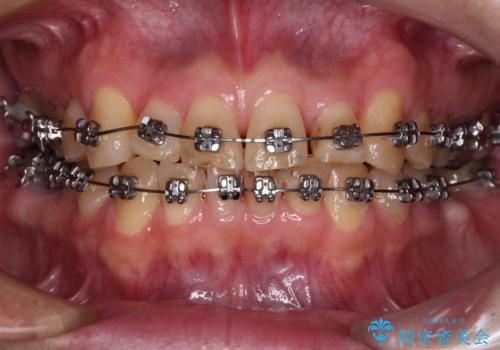

- 近医にてブリッジ治療を行った歯が痛くてたまらないとのことで来院された患者様です。

診察を行ったところ、奥の土台になっている歯は神経組織が失活しており、根尖部に病変があり、そこが原因で痛みを生じている状態でした。

根管治療を行うためにブリッジを除去したところ、むし歯が歯肉の奥深くにあまで及んでいたため、歯周外科処置によりむし歯が歯肉縁より浅い位置へと改善することとしました。

ここまでの治療を提案したところで、折角なのでしっかり治療を行いたいとのことで、前歯のデコボコやクロスバイトを改善するための矯正治療を行うこととしました。

まずは奥歯の痛みを改善し、その後矯正治療を行い、最後にオールセラミックブリッジによる補綴治療を行うこととしました。

むし歯をきっかけに矯正治療を行うこととなりましたが、学生の頃から気になっていた歯列を改善することができ、患者様には大変満足していただけました。